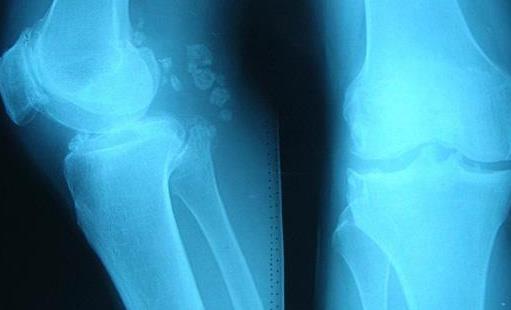

2、膝關節

膝關節在人體的眾多關節之中,承受的壓力是很大的,畢竟人體的自重都會積壓到這個關節之上,因此膝關節出現病變的幾率也是最高的,尤其是骨刺這種疾病。而對于膝關節有骨刺的患者來說,基本都會出現跛行和關節腫脹性疼痛的癥狀,當做體力勞動之時,這種癥狀會更加的明顯。